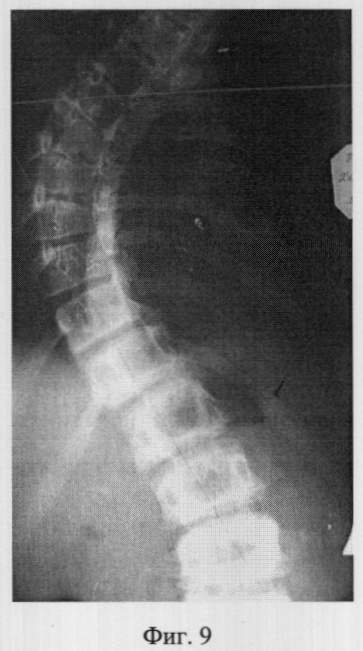

Фиг.9 – рентгенограмма в прямой проекции сколиотически измененного позвоночника больной X. до операции (грудная локализация);

В СарНИИТО ей были выполнена рентгенография в стандартных проекциях: фасная (фиг.9) и боковая (фиг.10) рентгенограммы.

По фасной рентгенограмме определены следующие показатели позвоночника:

– угол сколиотической деформации по Кобб: стоя – 50°, лежа – 48°;

– индекс стабильности по Казьмину – 0,82;

– определена протяженность дуги в 7 позвонков (от Th3 до Тh11),

– определена вершина деформации – Th6.